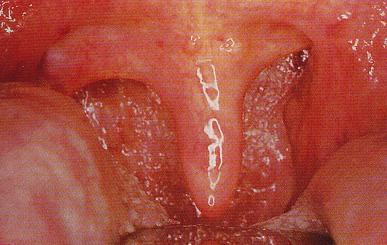

扁桃体脓肿

临床上,根据扁桃体肿大的病情轻重,把扁桃体肿大分为三度:

I度:扁桃体肿大不超过咽腭弓

II度:超过咽腭弓

III度:肿大达咽后壁中线